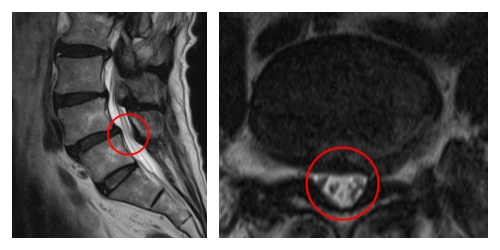

┃検査・診断

赤い枠で示されている部分(L4/5 )にヘルニアが認められました。

術前の腰痛を10とすると、術後およそ2週間で5まで軽減され、こわばりも和らぎました。4ヶ月後の経過観察では、さらに2まで腰痛が改善しています。